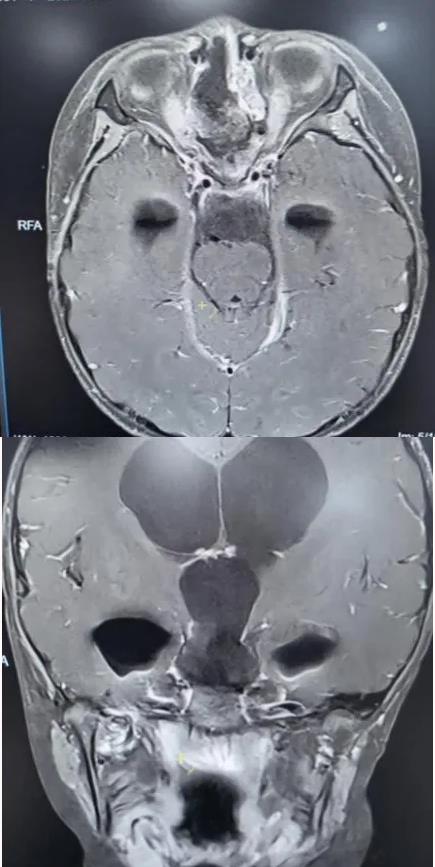

术前核磁共振检查

为精准掌握肿瘤情况,团队为欢欢完善了垂体MRI平扫+增强检查及相关激素水平检测。结果显示:肿瘤体积超过4厘米,形如鸡蛋,已严重压迫视神经与垂体,突入第三脑室,并与周围重要神经血管结构紧密粘连。颅咽管瘤是一种起源于颅底的先天性良性肿瘤,因体积大、位置深,且毗邻下丘脑、视神经、垂体等重要结构,手术切除难度极高,稍有不慎就可能导致失明、终身内分泌紊乱甚至有生命危险。